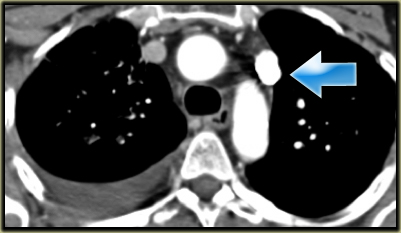

Left Superior Vena Cava

- Represents persistent left common cardinal vein

- Passes anterior to left main bronchus and drains into dilated coronary sinus

- 0.5% of general population and 5% of patients with congenital heart disease

- Small Right SVC in 90% of cases

On the left side there is a vascular structure, that runs inferiorly below the level of the left hilum and enters into a dilated coronary sinus.

The diagnosis is left or double superior vena cava.

On the left another example of a left superior intercostal vein.

It courses along the lateral margin of the aortic arch from the the accessory hemiazygos vein to the left brachiocephalic vein.